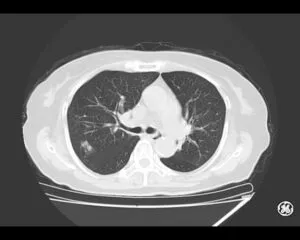

CT

GE社製Revolution ACT(16列)を導入しています。X線を利用して体の断面(輪切り)を撮像する検査です。この輪切りの画像をコンピューターで処理することにより、様々な方向からの断面像や3D画像を得ることができます。

CTで検査した画像